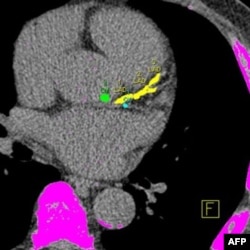

Türkiye ve ABD dahil tüm dünyada ölüm nedenlerinin başında gelen kalp ve damar hastalıkları geliyor. Bu hastalıkların önceden fark edilmesini sağlayacak testler hayat kurtarıyor. Kalp krizi riskini öğrenmenin en kolay yolu uzmanlara göre “kalsiyum skorlaması”. Modern cihazlarla, ilaçsız ve çok kısa sürede yapılabilen kalsiyum skorlaması, dört yıl içinde kalp krizi geçirme riskinin derecesini ortaya çıkarıyor.

Modern cihazlarla, ilaçsız ve derin bir nefes alma süresinde yapılabilen kalsiyum skorlaması, kalp damarlarındaki kireçlenme miktarını ve buna bağlı olan koroner arter hastalığı riskini ortaya çıkarıyor. Kalsiyum skorlaması sonuçları, kişinin gelecek yıllarına ilişkin bilgi veriyor.

Kalsiyum skorlamasında istenen, sonucun sıfır olması. Sonuç sıfır değilse, damardaki kalsiyum birikiminin miktarına göre kişide düşük, orta ya da yüksek derecede kalp damar hastalığı riski olduğu düşünülüyor ve çıkan sonuca göre ilaçla tedaviye başlanıyor. Ciddi bir damar tıkanıklığı olduğu belirlenenlereyse koroner anjiyografi uygulanıyor.

Hastaya ağızdan veya damardan hiçbir ilaç verilmeden, bilgisayarlı tomografiyle sadece bir tutumluk nefes süresinde yapılan kalsiyum skorlaması, uzmanlara göre en önemli tarama testlerinden biri. Modern cihazlarla yapılan ölçümle daha az radyasyon alınıyor.